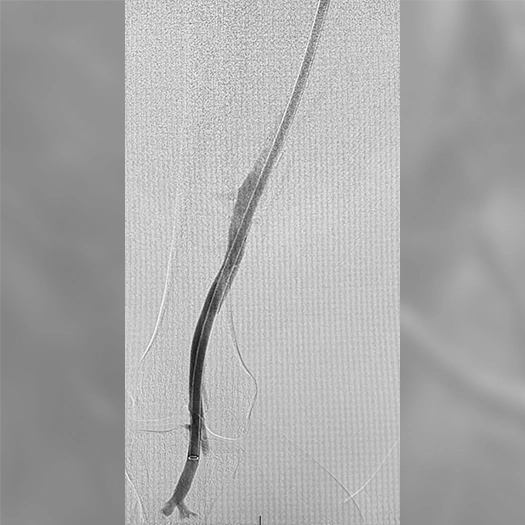

Pulmonary Embolism Cases

Venous Cases

Images used with permission and provided for illustrative purposes only. Procedural techniques and decisions based on physician’s medical judgment. Individual results may vary. Consents on file at Penumbra, Inc.